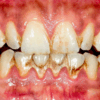

- Post‑eruptive stage – Surface may develop brown stains, pitting, or wear over time, especially with acidic diets.

- Severe – Marked brown stains, pitting, and enamel loss; may affect function.